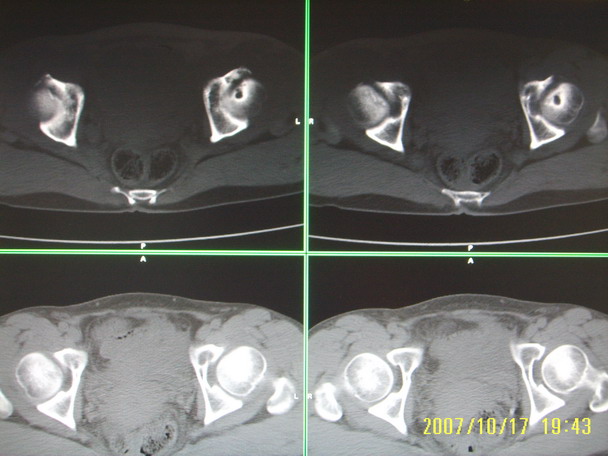

标题: CT10352:女,45岁,股骨头病变,如何诊断? [打印本页]

标题: CT10352:女,45岁,股骨头病变,如何诊断?

股骨头病变,如何诊断?

患者女,45岁,左髋部行走疼痛一年,无外伤史,无感染史。x片示囊状骨透亮区

左侧股骨头变形,密度增高,局部塌陷。多考虑:股骨头缺血性坏死伴退变!

左侧股骨头塌陷,其内囊变硬化,骨纹理改变考虑:左侧股骨头坏死及蜕变.

股骨头形态尚可,骨皮质环厚度及完整性可,病灶区以外骨质尚未见明显异常,临近髋臼骨质亦可见类似改变,考虑退变性关节面下囊变可能性大,骨样骨瘤等不排除,

两侧髋臼结构发育不良伴退行性改变.不除外色素沉着绒毛结节性滑膜炎.

支持成人髋臼发育不良继发髋关节退行性变

髋关节发育不良,左髋关节退变,左髋关节邻关节囊肿

股骨头形态尚可,骨皮质环厚度及完整性可,病灶区以外骨质尚未见明显异常,临近髋臼骨质亦可见类似改变,考虑1.动脉瘤样骨囊肿,2.股骨头缺血坏死,

股骨头形态尚可,骨皮质环厚度及完整性可,病灶区以外骨质尚未见明显异常,临近髋臼骨质亦可见类似改变,考虑退变性关节面下囊变可能性大

双侧股骨头形态都欠规整,外形欠光滑,尤以左侧明显,考虑双侧髋臼发育不良并退行性变